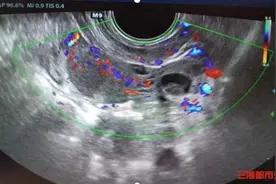

据西安市儿童医院公众号26日消息:5岁的彤彤(化名)因跳绳后下腹部疼痛难耐,当地医院初步诊断为急性阑尾炎。急诊来该院进一步复查B超,超声科医生却发现了更为严重的问题——卵巢扭转。医院随即安排进行急诊手术,术中发现右侧卵巢发紫,顺时针扭转720°,即对右侧卵巢进行了切除。